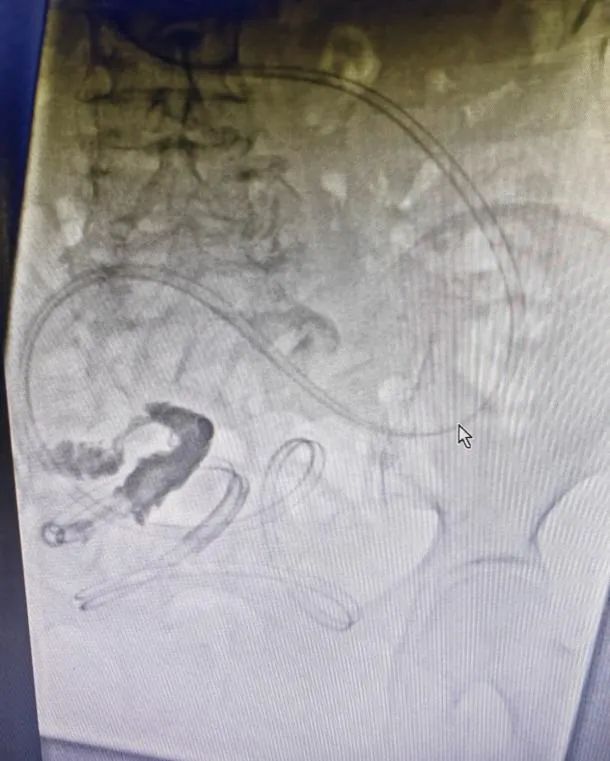

DSA下腸梗阻導(dǎo)管置入(rù)術

案例:患者,女,78歲,因“反複腹部脹痛伴肛門停止排(pái)氣排便3年”入院(yuàn),既往有闌尾切除術、輸尿管結石切開(kāi)取石術、輸卵管結紮術(shù)、鼻咽癌放療(liáo)史,有多(duō)次腸梗阻住院(yuàn)保守治療史,結合CT等(děng)檢查,診斷為粘連性腸梗阻,入院後禁食、解痙、抗感(gǎn)染、補液等對症支持(chí)治療(liáo)後,症狀未見明顯緩解,且腹脹逐漸加重,在(zài)DSA下消化道造影及腸梗阻導管置入,術後第二(èr)天梗阻緩解,肛(gāng)門排氣排便(biàn),從而進食,待腸道功能完全(quán)恢複後擇期行腹腔鏡(jìng)下腸粘連鬆(sōng)解術,術後6天(tiān)治愈(yù)出院。

腸(cháng)梗阻導管置入時造影片

梗阻解除(chú)後複查造影(yǐng)片,見梗阻部位